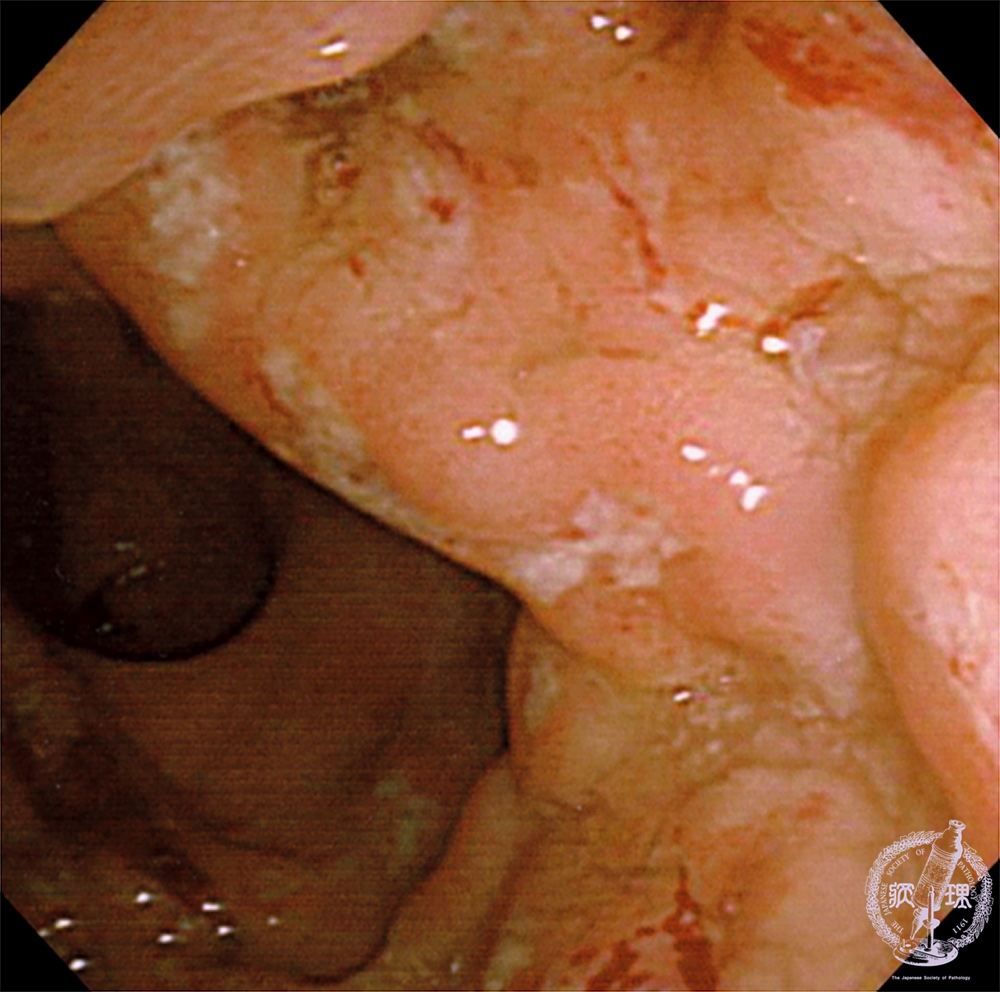

Gross appearance (endoscopic view): Within ulcers, there is patchy hemorrhage imparting a red color.